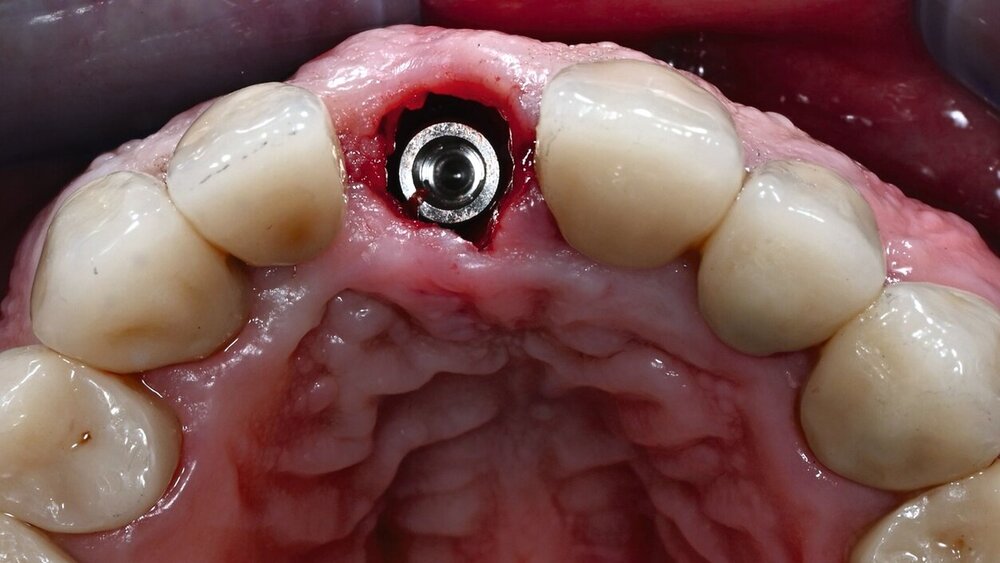

Ausgeschlossen wurden neben Patienten, die aus Gründen ihrer Allgemeinanamnese nicht für eine Studienteilnahme infrage kamen, Bruxer, Patienten mit Parodontitis und Raucher (mehr als zehn Zigaretten pro Tag). Alle Zähne wurden nach der DVT-Planung möglichst atraumatisch entfernt und die Alveole kürettiert. Die Höhe des bukkalen Knochens wurde klinisch mit einer Parodontalsonde gemessen. Die Implantatlager wurden frei Hand möglichst nach palatinal aufbereitet. Bevor das Implantat eingesetzt wurde, wurde der letzte Implantatbohrer in die Alveole gegeben und der Raum zwischen Bohrer und Alveolenwand mit einem Knochenersatzmaterial aufgefüllt (Bio-Oss, Geistlich Pharma AG, Wolhusen, Schweiz). Dann wurde der Bohrer entfernt und das entsprechende Implantat (Nobel Active, Nobel Biocare, Karlskoga, Schweden) eingesetzt. Es wurde darauf geachtet, dass die Implantatschulter 3 bis 4 mm unter dem bukkalen Weichgewebe lag.

In derselben Sitzung wurde eine provisorische, verschraubte Krone eingesetzt. Neben einer präoperativen Gabe von 2 g Amoxicillin erhielten alle Patienten ein Antibiotikum für fünf postoperative Tage. Drei bis neun Monate nach Implantation wurde die provisorische, verschraubte Krone durch eine zementierte Krone auf einem individuellen Abutment oder einer definitiven verschraubten Krone ersetzt. Das ästhetische Ergebnis wurde zu fünf Zeitpunkten beurteilt: vor und nach dem Eingriff (Zeitpunkte T0 und T1), nach Eingliederung der definitiven Krone (T2), nach einem Jahr (T3) und nach drei Jahren (T4). Auf dem postoperativen DVT (T1) wurde der Spalt zwischen der Innenwand des bukkalen Knochens und dem Implantat ausgemessen. Weiterhin wurde auf einem nach Eingliederung der definitiven Krone angefertigten DVT die Form des Abutments als konvex oder konkav klassifiziert.